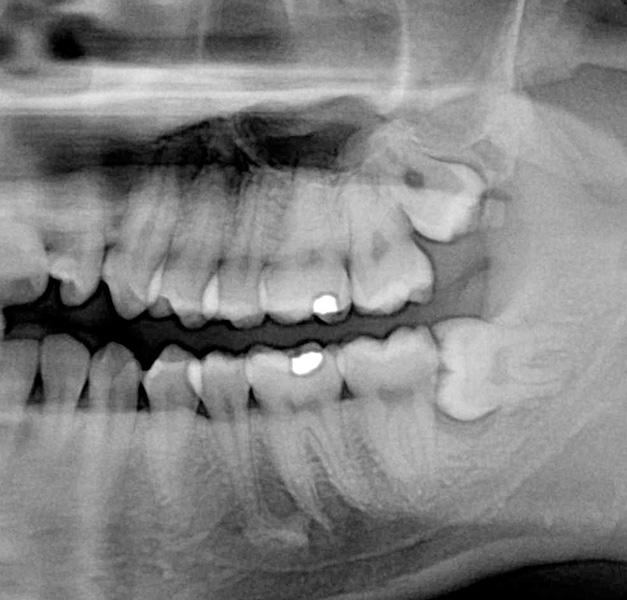

Zuby moudrosti (lidově „osmičky“) se zakládají v čelistech jako poslední zuby kolem 8. roku života a zpravidla prořezávají do dutiny ústní po 17. roce života. Proto velice často není místo pro jejich zařazení do správné polohy a zůstávají částečně nebo úplně skryté v kosti. Mohou být různě skloněné či zdeformované. Dále mohou nepříznivě působit i na sousední zuby či okolní měkké tkáně kolem čelistí jako bolestivý zánět.